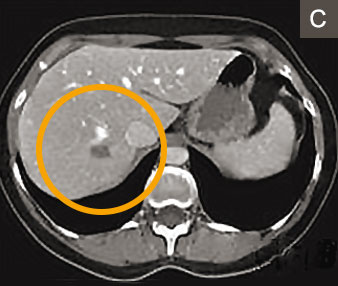

Alternativ oder ergänzend zur Leberteilentfernung können Lebertumoren auch mit einer Nadeltechnik 2 verödet werden. Dabei erzeugen Radiofrequenzen oder Mikrowellen hohe örtliche Hitze. Die Methode ist für nicht oberflächlich gelegene Lebertumoren bis zu einer Grösse von drei Zentimetern geeignet (Abbildungen A – C). Sie wurde vom Autor und seinem Team seit 15 Jahren angewandt und weiterentwickelt 3 und bietet folgende Vorteile: Es geht weniger normales Lebergewebe verloren als bei der Leberteilentfernung und der Eingriff kann ohne Bauchschnitt durchgeführt werden. Entsprechend ist die Nadeltechnik für die Patienten wenig belastend.

1 Jahr später: verödetes Areal ist geschrumpft, kein Tumorrückfall